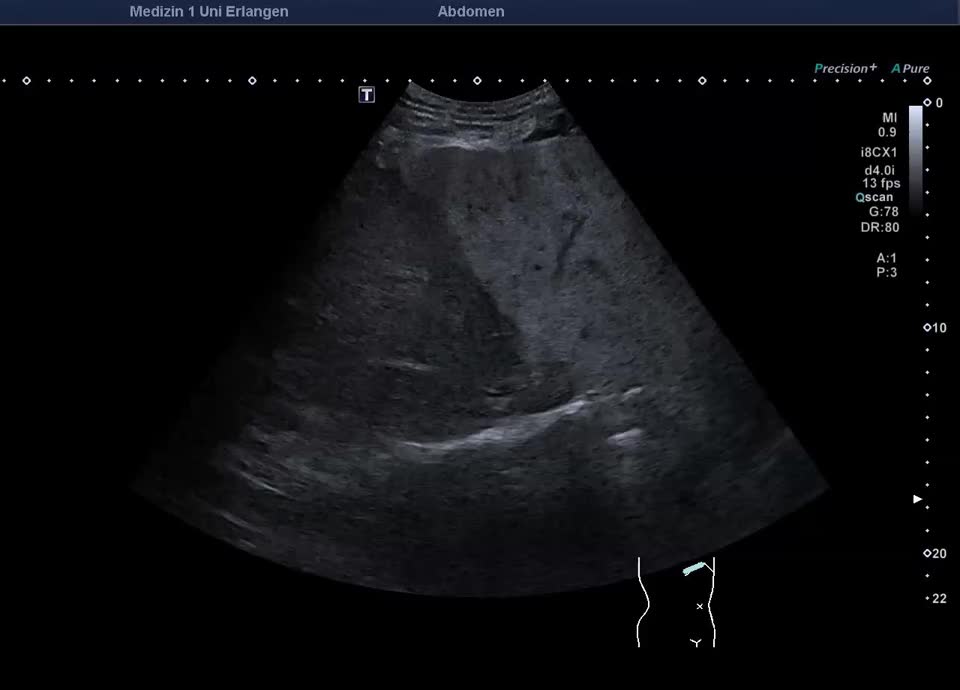

Lobuläre Mehrverfettung des rechten Leberlappens